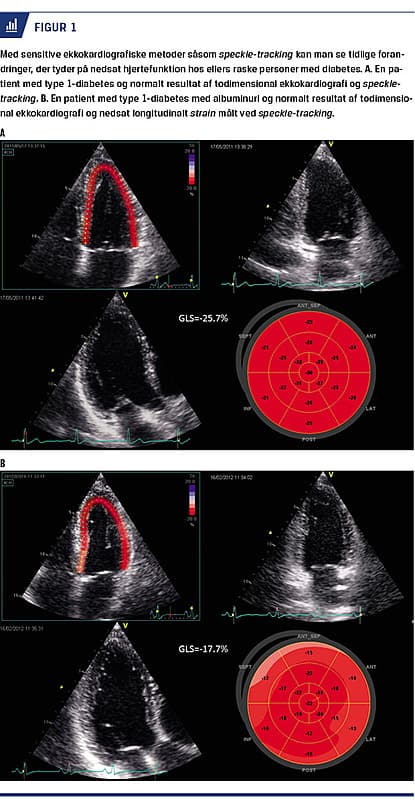

Det er påvist, at patienter, der har diabetes og albuminuri, har op til fem gange højere risiko for at få påvirket hjertefunktion end andre [6]. På Figur 1 kan man se, hvordan man med avanceret ekkokardiografi har detekteret diskret nedsat myokardiefunktion hos en patient, der har type 1-diabetes og albuminuri, sammenlignet med en patient uden albuminuri, trods normal EF hos begge patienter.